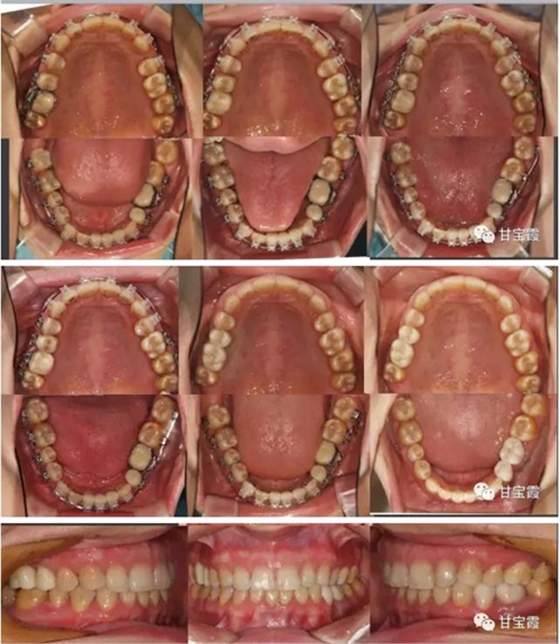

大家都知道以前缺一顆牙要鑲?cè)w烤瓷牙,缺兩顆要鑲六顆烤瓷牙,因而好好的一顆牙就因?yàn)殍偲渌辣荒サ袅艘粚?,十分可惜。這次就診根據(jù)患者口腔的檢查我制定了一個(gè)治療計(jì)劃:拆除九顆烤瓷牙,缺牙的部分用正畸的方法移動(dòng)牙齒,關(guān)閉缺牙間隙,不再鑲牙。下前牙的三顆聯(lián)排的烤瓷牙改成單顆修復(fù),這樣更符合生理。下面的系列圖片是治療過(guò)程,大家可以看到缺牙間隙是怎么一點(diǎn)一點(diǎn)關(guān)閉的。

經(jīng)過(guò)28個(gè)月的矯正,大家可以看到原來(lái)的兩個(gè)缺牙間隙沒(méi)有了,舊的烤瓷牙換成了全瓷冠修復(fù)。下面的圖片是矯正前后的X線對(duì)比,